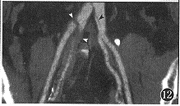

图12 中心线重组用于髂动脉的CTA,此例为主动脉夹层累及髂总动脉,可见左髂总动脉的内膜片(黑箭头),以及右髂总、髂内动脉的内膜片和血栓(白箭头)